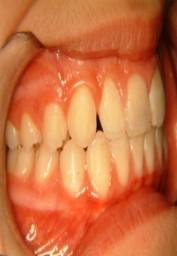

-Προγναθισμόs κάτω γνάθου

Πρώτη περίπτωση

Πριν Μετά

Εάν ο προγναθισμός της κάτω γνάθου δεν αντιμετωπιστεί σε νεαρή ηλικία τότε η διόρθωση του θα χρειαστεί και τη βοήθεια της γναθοπροσωπικής χειρουργικής, διότι όταν η ανάπτυξη τερματιστεί δεν γίνονται γναθικές αλλαγές κατά τη διάρκεια της ορθοδοντικής θεραπείας παρά μόνο μετακινήσεις φατνιακού οστού και δοντιών (19)